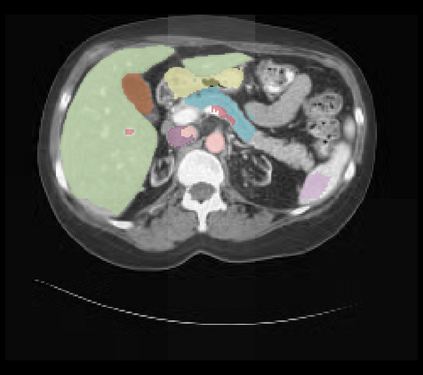

It is imperative to ensure the robustness of deep learning models in critical applications such as, healthcare. While recent advances in deep learning have improved the performance of volumetric medical image segmentation models, these models cannot be deployed for real-world applications immediately due to their vulnerability to adversarial attacks. We present a 3D frequency domain adversarial attack for volumetric medical image segmentation models and demonstrate its advantages over conventional input or voxel domain attacks. Using our proposed attack, we introduce a novel frequency domain adversarial training approach for optimizing a robust model against voxel and frequency domain attacks. Moreover, we propose frequency consistency loss to regulate our frequency domain adversarial training that achieves a better tradeoff between model's performance on clean and adversarial samples. Code is publicly available at https://github.com/asif-hanif/vafa.